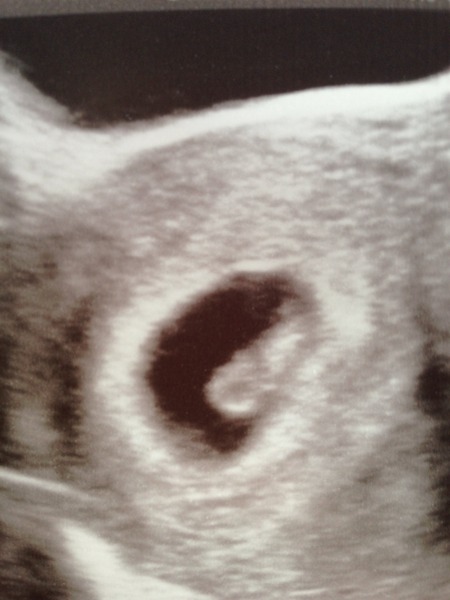

Hello guys, thank you for the support. Had a scan today, they could see the bleed but it was separate from baby who was in the right place with heartbeat Grin. So looking very positive at the moment!

That's great news Lemon so pleased for you. What a lovely scan pic.

Aposey · 31/10/2015 16:57

Amber it was at 2pm.

Just got back from the scan and I still cant quite believe it! It was extraordinary to see the tiny creature and even a little heart beat. Apparently despite my short cycles Im actually more like 7+2 than 7+6 so I feel like Ive gont back in time half a week! Im so impatient Blush

Lovely scan pic lemon! mrsmugoo you are exactly right - all this worry when the most likely outcome of any pregnancy is a perfectly healthy baby! It's a mantra I have to repeat to myself at least once a day Smile